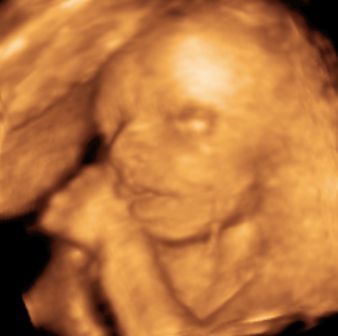

Na, és rakok fel pár képet: Btw: Tiszta apja! :)

Kép Megtalálta az ujját... Kép Cumizik :) Kép Nagyon cumizik :) Bal kezes lesz úgy tűnik. :) Kép Kép Turcsi nózi :)

nagyon helyes kis pofija van a babucinak, főleg a turcsiorros :)